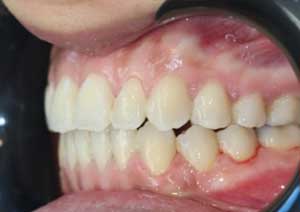

Traitement : Une ingression des molaires maxillaires avec une égression contrôlée du secteur antérieur a été réalisée à l’aide des arcs dits “Rocking Chair”, associés à des élastiques antérieurs portés de canine à canine, à droite et à gauche.

Cette mécanique permet de corriger la béance antérieure tout en conservant un contrôle précis de la position des dents antérieures et postérieures.

Après